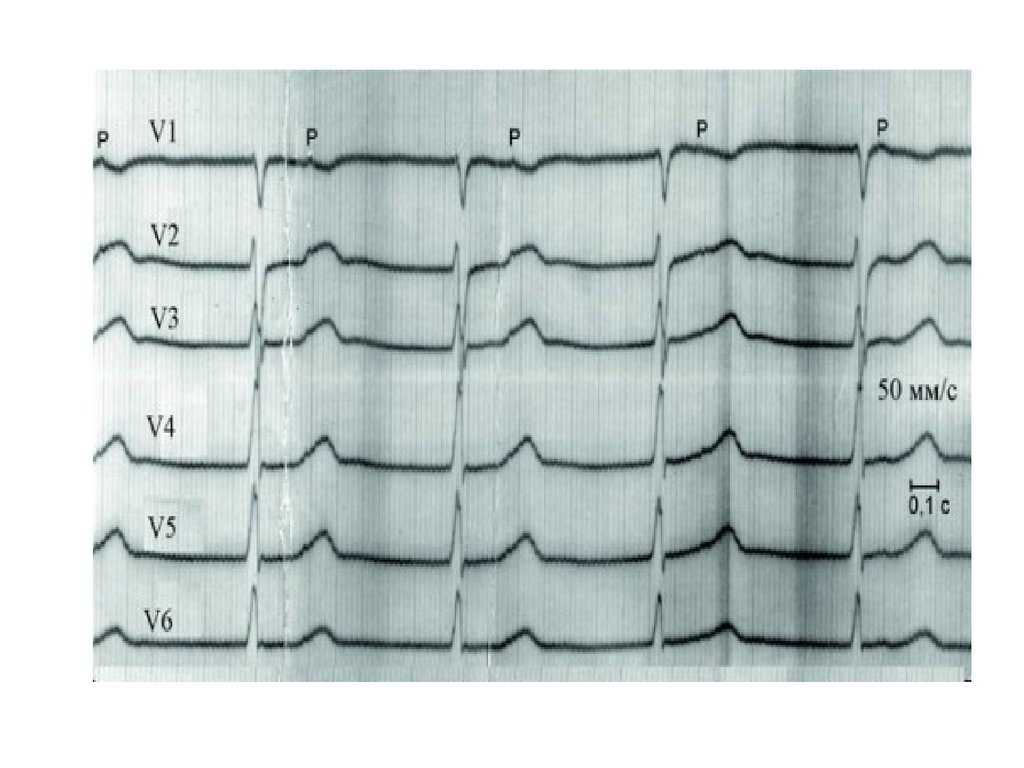

3.Может быть

АВ-блокада 3 ст. (полная поперечная блокада)

• Полное разобщение ритмов предсердий и

желудочков

• Интервалы Р-Р одинаковые

• Предсердный ритм реже желудочкового Р-Р

< R-R

• R-R = 20-40/мин. до 60 уд./мин

• Комплекс QRST не изменен

• Перегрузка обоих предсердий –

непостоянный признак